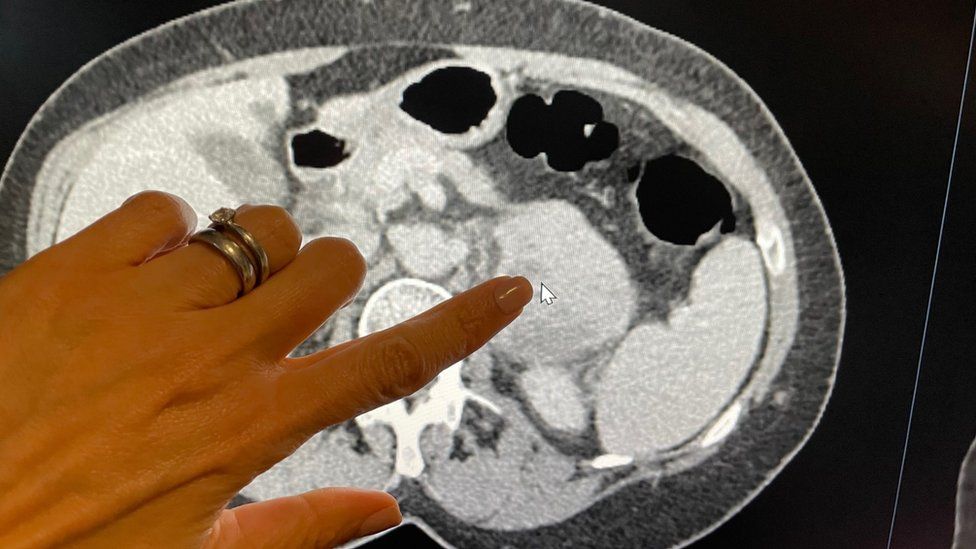

КТ ретроперитонеального фиброза: Изображения и диагностика